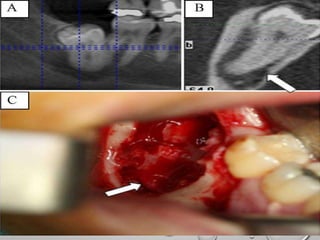

A.CORONECTOM

Y OF AN

IMPACTED 3RD

MOLAR WITH

NERVE

INVOLVEMENT.

B. ONE YEAR

LATER SHOWS

BONE

FORMATION AS

WELL AS ROOT

MIGRATION.

CORONECTOMY (PARTIAL TOOTHREMOVAL, PARTIAL ODONTECTOMY OR INTENTIONAL ROOT RETENTION) Angle of the bur at approximately 45° and lingual retractor protecting the lingual nerve (arrow). Shaded area of root on buccal side to be removed secondarily. Pogrel, Lee, and Muff. Coronectomy. J Oral Maxillofac Surg 2004

A.CORONECTOM Y OF AN IMPACTED3RD MOLAR WITH NERVE INVOLVEMENT. B. ONE YEAR LATER SHOWS BONE FORMATION AS WELL AS ROOT MIGRATION.